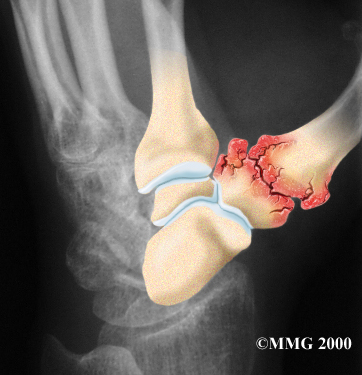

Degenerative Arthritis

Injury to a joint, such as a bad sprain or fracture, can cause damage to the articular cartilage. An injury to the CMC joint of the thumb, even if it does not injure the articular cartilage directly, can alter how the joint works. After a fracture of the thumb metacarpal, the bone fragments may heal in slightly different positions. The joints may then line up differently. This is also true when the ligaments around the CMC joint are damaged by a sprain. When an injury results in a change in the way the joint moves, the injury may increase the forces on the articular cartilage surfaces. This is similar to any mechanical device or machinery. If the mechanism is out of balance, it tends to wear out faster.

Over many years this imbalance in the joint mechanics can lead to damage on the articular surface. Since articular cartilage cannot heal itself very well, the damage adds up. Eventually, the joint is no longer able to compensate for the increasing damage, and it begins to hurt. Damage has occurred well before the pain begins.